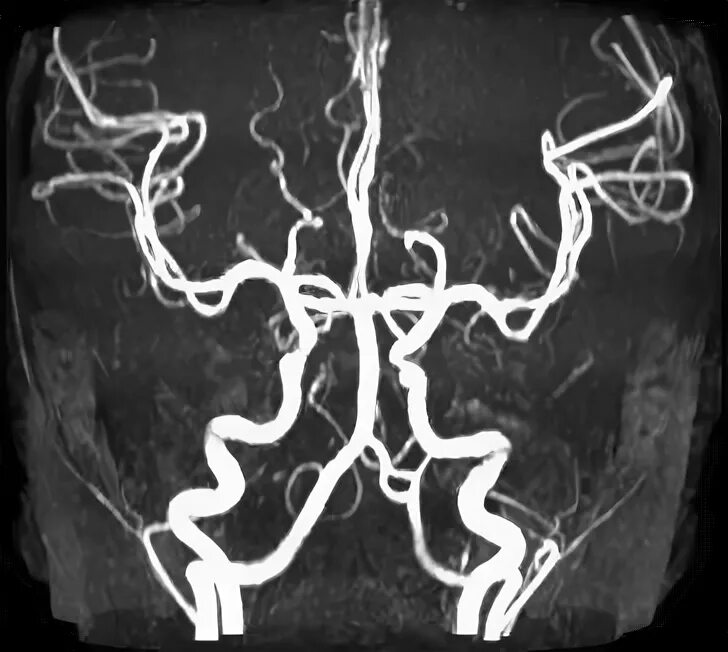

Гипоплазия интракраниального сегмента